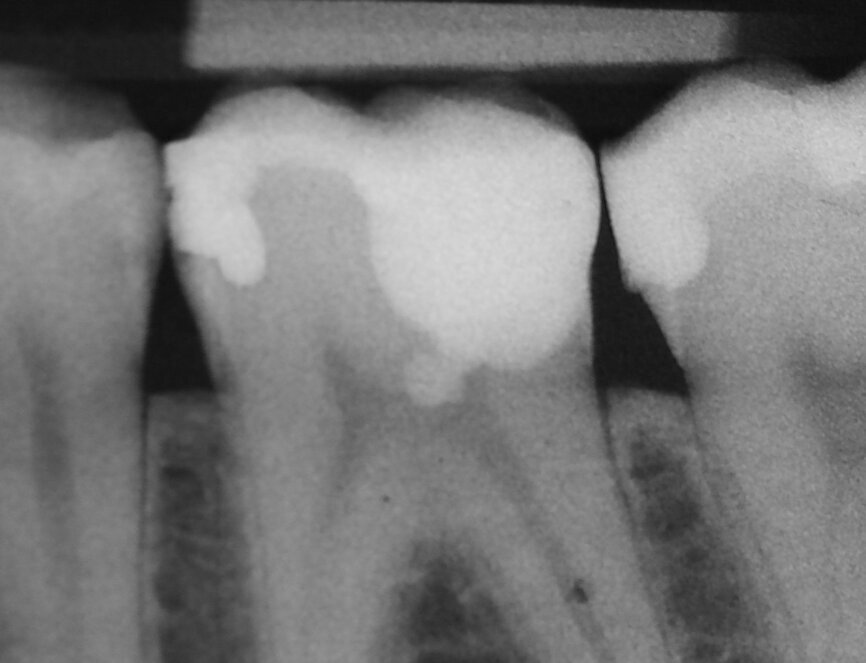

Vital pulp therapy has become more popular in recent years. Calcium hydroxide has been the most common material for pulp capping, but MTA has shown even better results in biocompatibility and outcome.[3] Cases with large carious pulp exposure can be treated successfully with partial pulpotomy and MTA as a capping agent, keeping teeth vital (Figs. 1a–e).

Fig. 1a: (a) Deep carious lesion. (b) Partial pulpotomy. (c) MTA application with the MAP System and PD MTA White. (d) Filling. (e) Post-op radiograph showing the pulp capping with MTA.

Fig. 1b: (a) Deep carious lesion. (b) Partial pulpotomy. (c) MTA application with the MAP System and PD MTA White. (d) Filling. (e) Post-op radiograph showing the pulp capping with MTA.